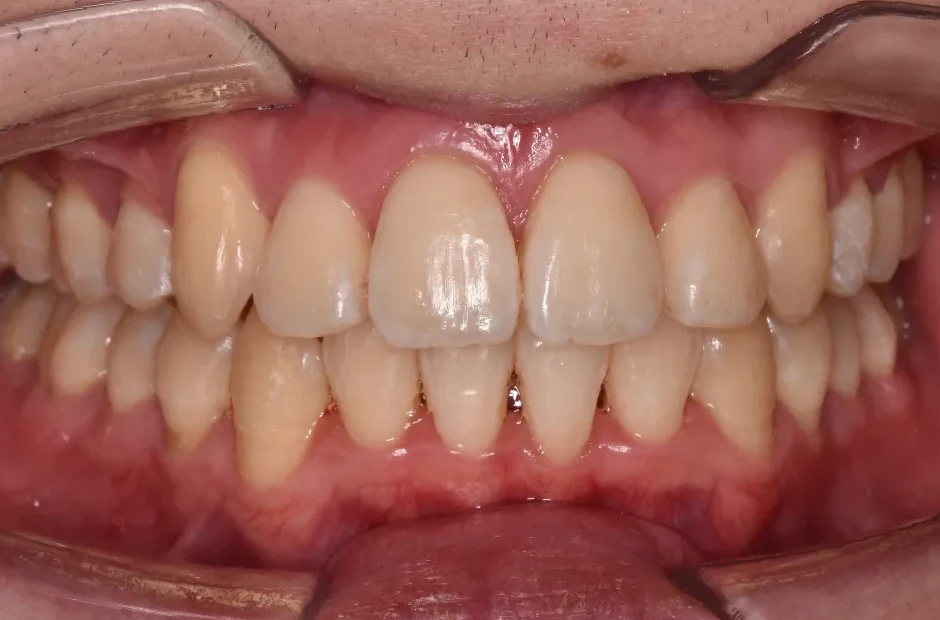

ブラケット矯正

前歯部反対咬合

| 診断名・主訴 | 前歯部反対咬合 |

|---|---|

| 年齢・性別 | 14歳・男性 |

| 治療期間・回数 | 1年2か月 |

| 治療に用いた主な装置 | ブラケット矯正 |

| 抜歯部位 | なし |

| 治療費 | 60万円(税抜) |

| リスク・副作用 | 装置による違和感・疼痛・歯肉退縮・歯根吸収・虫歯のリスクなど |

治療後